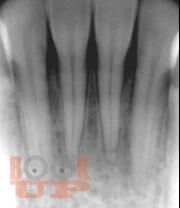

Представление материала сопровождается авторскими рисунками, фотографиями данными рентгенологических методов исследования, описанием клинических примеров.